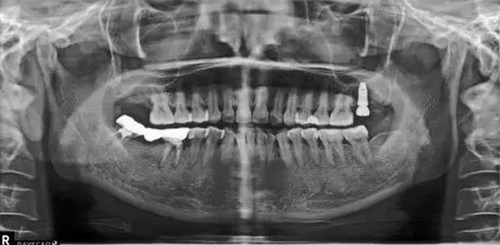

種植術(shù)后三個月復(fù)查X片??梢娮笊戏N植體已植入?;謴?fù)良好。開始著手進行修復(fù)進行二期手術(shù)。